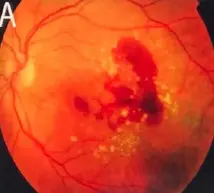

Wet macular age related degeneration

Male nondiabetic patient aged 75 years old presented by this picture in the left eye

What is treatment in this condition? Intravitreal injection of AVGF

Fundus:

- Wet: gray-yellow CNV under retina of posterior pole, associated with dark red subretinal hemorrhage, which covers CNV sometimes

FFA: CNV leakage, bleeding

- Disciform scar formation under macula, bleeding and leakage of CNV